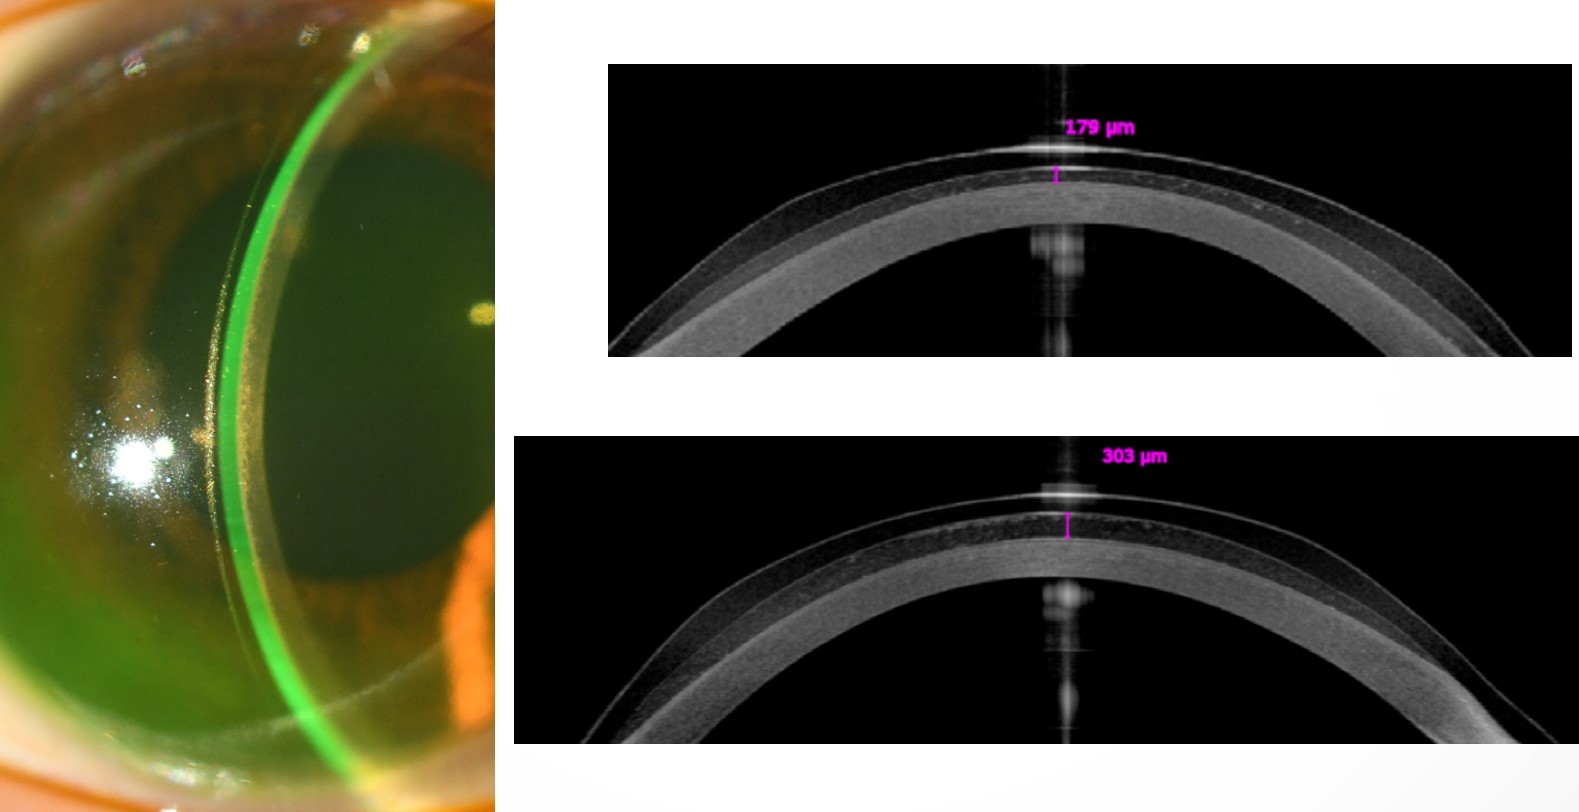

UV-A는 각막내피에 독성을 일으킬수 있어 각막기질 두꼐가 400um이상으로 충분히 두꺼운 경우에 시행합니다.